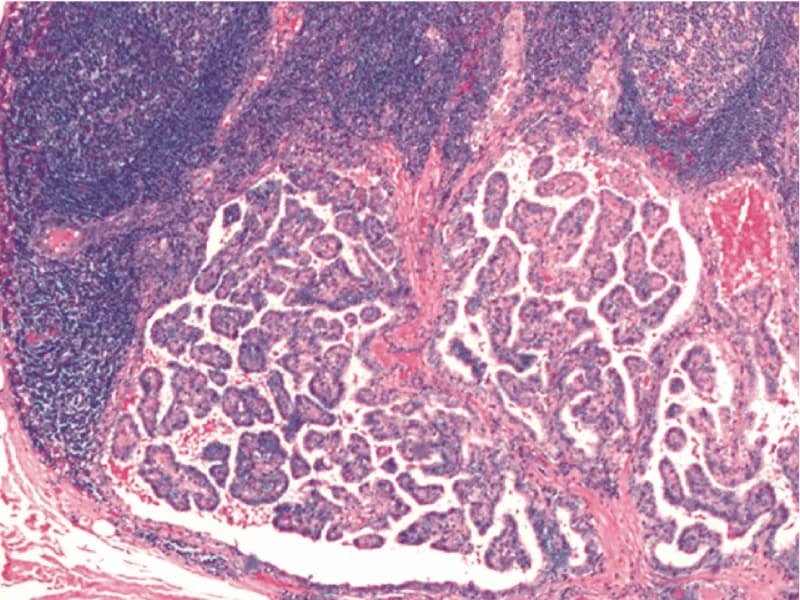

Tireoglobulina e anti-tireoglobulina

Tireoglobulina é uma proteína produzida exclusivamente pela tireoide para armazenar iodo. A vantagem desse exame é que, quando a tireoide é removida, o exame de sangue não detectará nada de tireoglobulina e ficará zerado, na maioria dos casos. Esse exame é extremamente importante pois, quando ele começa a subir, é um sinal bem precoce de que a doença vai recidivar, permitindo tratamento precoce e chance de cura ainda muito boa.

A anti-tireoglobulina é um anticorpo que ataca a tireoglobulina, comum nos pacientes que têm tireoidite de Hashimoto. Na maioria dos pacientes ela é negativa, mas quando positiva ela atrapalha a dosagem da tireoglobulina no seguimento do câncer, pois faz com que o exame de tireoglobulina dê negativo sem realmente ser negativo. Nesses casos acompanhamos os valores de anti-tireoglobulina para prever se a doença vai recidivar ou não, mas não é tão confiável quanto a tireoglobulina.